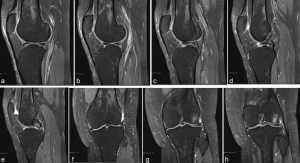

A 35-year-old female presented to our institution with left knee pain. She has a history of a meniscus tear from 16 years ago, which was managed nonoperatively at the time due to minimal symptoms. Over the past month, her pain has become significant. There has been no new injury. She reported pain on both the medial and lateral aspects of her left knee, accompanied by swelling. The pain worsened with squatting and had been experiencing instability and intermittent locking in the knee. In addition, she felt instability in her knee for about a year and a half, which has prevented her from exercising. On examination, the patient exhibited a normal gait and a full range of motion. On the left knee, there was mild tenderness and mild effusion along the lateral joint line and slight pain with flexion during the McMurray test. Perioperative MRI demonstrated a complex bucket-handle tear through the anterior horn into the body of the lateral meniscus with flipped torn meniscal fragments medially into the tibiofemoral joint space (Fig. 4).

Figure 4: (a-e) Series of sagittal magnetic resonance imagings (MRIs) of Patient 2 displaying a sequence from lateral to medial. The anterolateral meniscofemoral ligaments can be seen continuing from the anterior horn on the lateral meniscus and inserting into the anterior cruciate ligament footprint. This was interpreted as a flipped bucket handle tear prior to surgery. (f-h) Series of coronal MRIs of Patient 2 displaying meniscal tissue within the intercondylar notch. On re-review, the anterolateral meniscofemoral ligament can be seen inserting into the lateral aspect of the intercondylar notch.

During arthroscopy, there were grade 1–2 changes in the patellofemoral compartment and grade 2 changes in the medial compartment. A radial tear noted in the midsubstance of the medial meniscus was debrided to stable edges. There were grade 2 and minor grade 3 changes in the lateral compartment. The lateral compartment showed abnormal meniscal anatomy evidenced by a partial discoid meniscus with a large intra-meniscal attachment connecting the anterior and posterior horns through the notch. This portion was unstable and mobile, while the midportion of the meniscus in its normal location had complex tearing. The midsubstance of the meniscus was debrided to stable edges, performing a partial meniscectomy. The unstable intra-meniscal attachment connecting the anterior and posterior horns was also debrided. In addition, a separate attachment from the anterior horn of the lateral meniscus to the native ACL origin on the medial aspect of the lateral femoral condyle was found (Fig. 5). This anomalous tissue was debrided. The anterior horn was attached to the root and was stable, and the posterior horn had a partial root attachment and a large meniscofemoral ligament attachment, making it stable. There was no evidence of ACL present in the notch, but the bony anatomy of the notch was normal. Therefore, the decision was made to debride the redundant tissue, restoring normal meniscal shape. On post-operative review of the patient’s MRI, the ALMFL could be appreciated on both the coronal and sagittal images inserting into the native ACL footprint (Fig. 4).